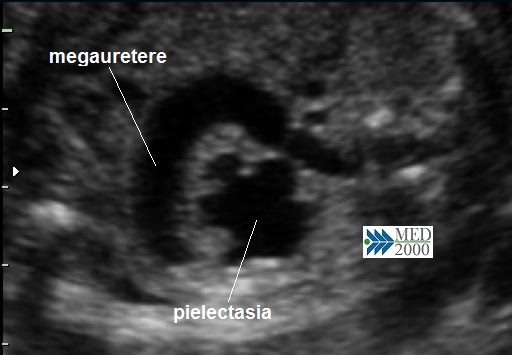

• megauretere: si presenta come una struttura tubulare a decorso rettilineo o tortuoso tra pelvi renale e vescica; il color doppler può aiutare a distinguerlo da strutture vascolari e la continuità con la pelvi renale spesso dilatata lo distinguono dalle anse intestinali. Spesso il megauretere è un segno tardivo per cui il riconoscimento definitivo avviene nel terzo trimestre o alla nascita.

• pielectasia e calicectasia: consiste nella dilatazione della pelvi o bacinetto e dei calici; la diagnosi di pielectasia è effettuata allorquando il diametro antero-posteriore della pelvi è superiore ai 7 mm. Nelle forme severe di pielo-calicectasia si ha compressione del parenchima renale con successiva corticalizzazione.